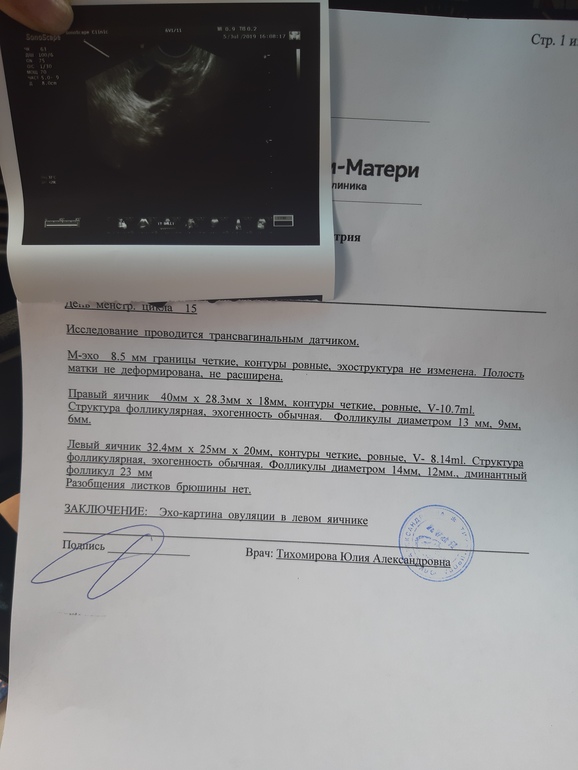

Овуляция по узи плюс тест

Пришла я на фоликулометрию.

И знаете что, мне говорят у вас на данный момент овуляция !

Хм,как это она углядела? Если О,то наверно ЖТ должно появляться и жидкость из фоллика выходить?

А кто его знает ,она сказал вот она у вас уже лопнула, и на фото круглое это яйцеклетка 🙈

Если фоллик лопнул,то сразу образуется ЖТ. Если он лопнул,почему тогда объем жидкости не указала. У меня в дневнике есть запись,я тоже ходила на Узи и тоже сказали день Овуляции)) тест тоже полож. Удачи нам!